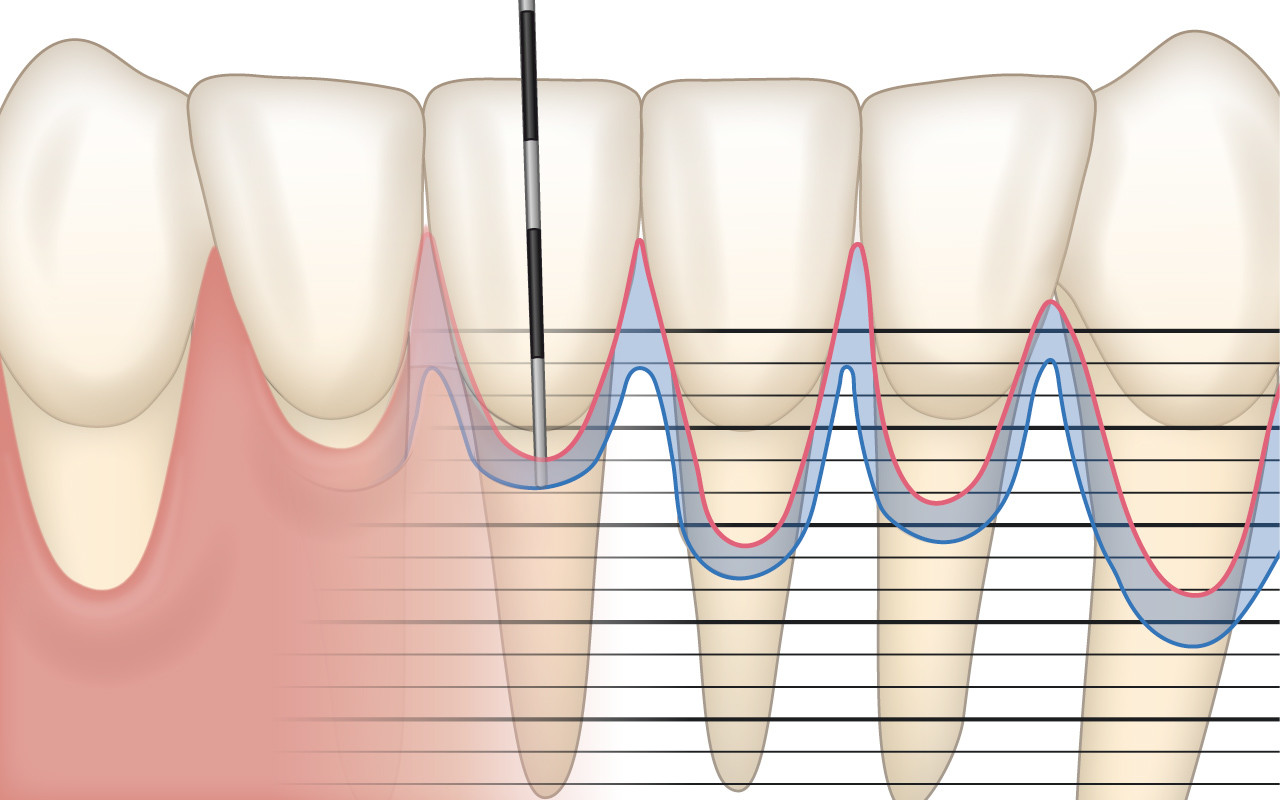

Parodontalstatus

Die millimetergenaue klinische Sondierung mit der Zahnfleischsonde zur Ausmessung der Zahnfleischränder und zur Lokalisierung des Kieferknochens sind für die Diagnose einer Zahnfleischrezession unverzichtbar.

Bei der klinischen Untersuchung mit der Zahnfleischsonde (Parodontalsonde) wird an bis zu sechs Stellen pro Zahn millimetergenau die Eindringtiefe der Sonde in die Zahnfleischtasche gemessen. Genaugenommen wird die Länge zwischen dem Zahnfleischrand und dem Boden der Zahnfleischtasche ausgemessen. Es wird dabei von der sogenannten Sondierungstiefe gesprochen. An gesunden Stellen wird die Sondierungstiefe höchstens 3 mm betragen. An Stellen, wo durch die Zahnfleischrezession auch die Zahnverankerung bereits abgebaut worden ist, wird die Sondierungstiefe jedoch auch nur wenige Millimeter betragen.

Zusätzlich wird in einem sogenannten Parodontalstatus die Höhe des Kieferknochens (Attachmentniveau) millimetergenau festgehalten. Ein Parodontalstatus ist zur Diagnostik und Behandlungsplanung einer Zahnfleischrezession unverzichtbar. Der Parodontalstatus kann in jeder Zahnarztpraxis online kostenlos aufgezeichnet und weiterverwendet werden: www.parodontalstatus.ch.